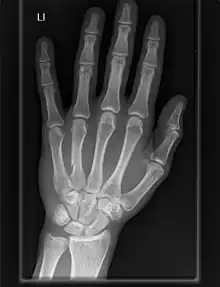

Section through the human wrist

X-ray of a human hand